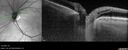

73-year old female - She had no visual complaints. She did notice a gradual decline in vision in the left eye. She also had cataracts. She was seeing the optometrist for glasses so no scans were done. She was told there might have been a decline from the cataracts. This started about 3-4 years ago. She was first noted to have swelling in the left eye one year ago. There was a possibility of something else so the patient had 3-4 Eylea injections October - December of 2021. Since then, she has not had any treatment (this was one year ago). She has been watching the left eye for change. If the vision were to get worse, then further treatment, like vitrectomy, could be considered. She lost hearing in the right eye ear and has been on oral prednisone for that. Medical Hx: Ear Steroid Injections x 5. Pure Hypercholesterolemia, Unspecified. Ocular Migraines. GERD. Gall Stones. Tinitis. Surgical Hx: Hysterectomy. Knee Surgery. Systemic Meds: Valacyclovir 1 Gram BID. ATORVASTATIN. CLONAZEPAM. ESTRADIOL. Imitrex. Methocarbamol. Omega 3. OMEPRAZOLE. Topiramate. VA 20/25 OD, 20/32 OS IOP 23,23 3+ Nuclear sclerotic cataract With 3 years follow-up the vision and the macula are stable.

Macular schisis with no leakage on FA - Presumed Nerve pit maculopathy99 views73-year old female. Had treatment trial with Eylea with no benefit (4 months). Vision is 20/32 in left eye and has remained there (with a dense cataract).00000